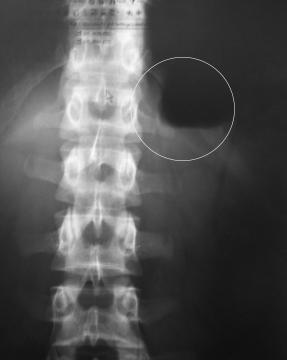

Nedávno som bol na snímku RTG, išlo o snímok spojený z bolesťou v bedrovom kĺbe, na snímku som doma objavil dosť veľkú čiernu škvrnu, neviem o čo ide. Chcem sa opýtať, či je to v poriadku že tam je, či nejde o nejaký problém, alebo chorobu.

Dobrý den,Jde o artefakt tj. strukturu, která se zobzazovanou částí nesouvisí. Nejde o projev žádné choroby, ale o "chybu" na RTG snímku.